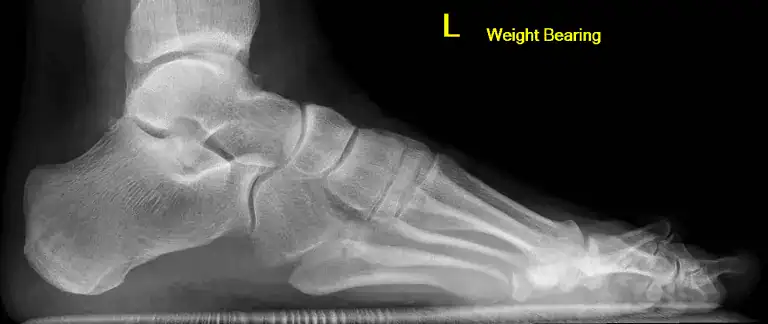

Midfoot arthritis is where there is a reduction in one or many of joint spaces within the midfoot.

Moderate arthritis of the joint of the navicular and medial cuneiform

Normal left foot